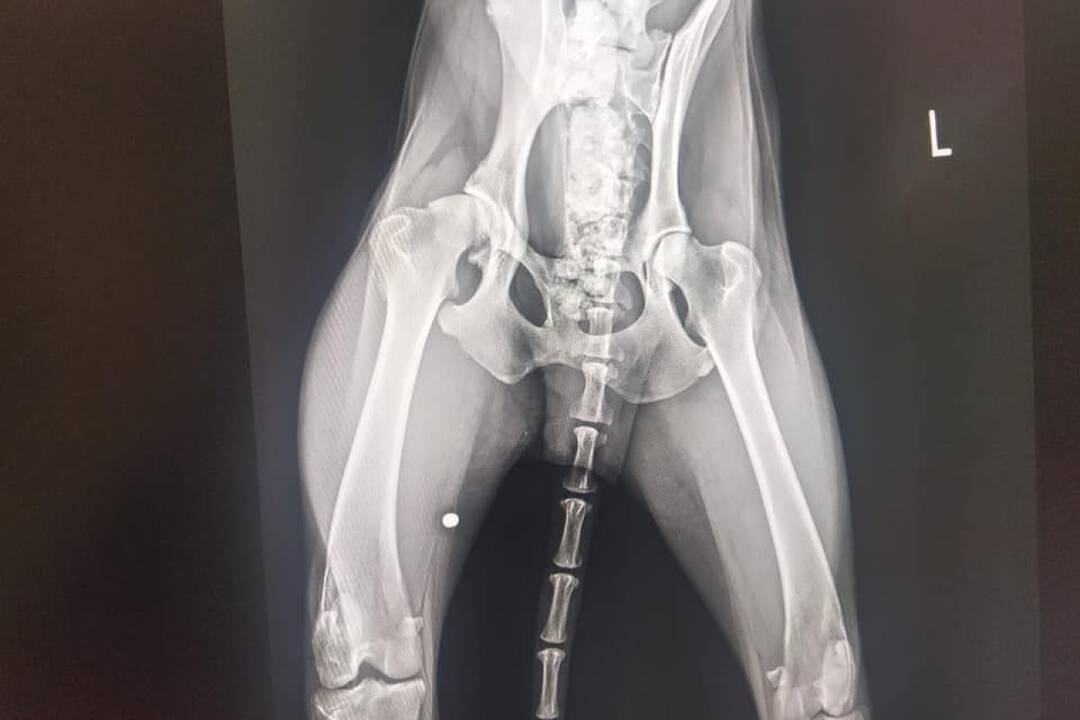

FOTO: Utýraný a vyhladovaný Odin mal v tele starší brok

FOTO: Utýraný a vyhladovaný Odin mal v tele starší brok, foto 5

Zdroj: Facebook/Sloboda zvierat